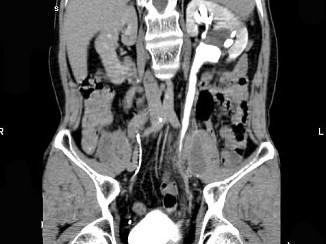

问题 男,59岁,反复尿频尿急尿痛4年余,尿常规检查:红细胞(+),白细胞(++),CT扫描如图示,下列说法正确的是 ( )

选项 A、考虑为慢性输尿管炎 B、考虑为输尿管移行细胞癌 C、左侧侧输尿管上段扩张 D、考虑为输尿管结核 E、左侧输尿管中下段输尿管管壁增厚,管腔狭窄

答案 ACE